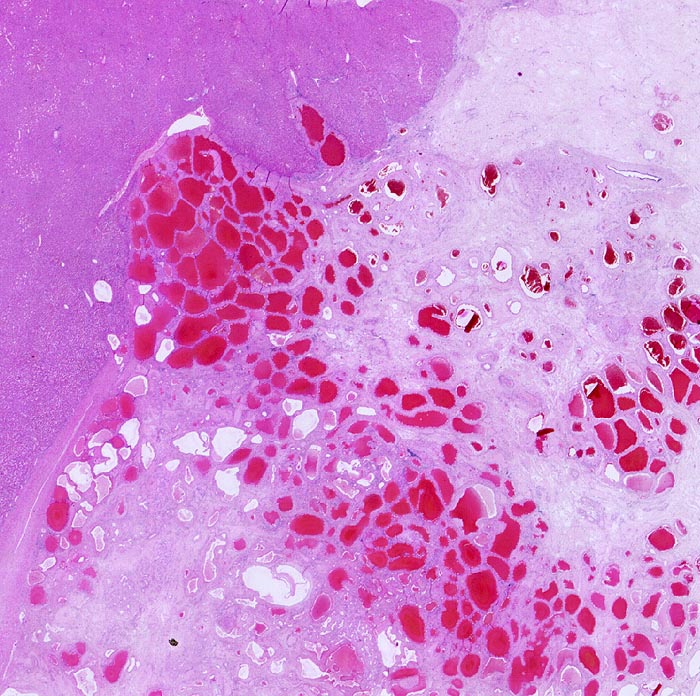

Hämangiom

benigner Tumor

Leber

Makroskopie

Befund

Pathologischer Befund